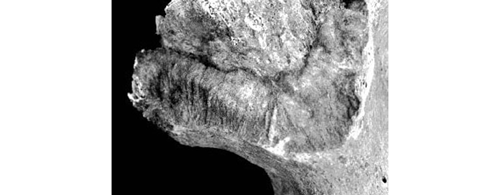

SSPID (Modification de la Tubérosité Iliaque)

Région postérieure à la surface auriculaire (insertion du ligament interosseux sacro-iliaque). Les formations osseuses (remaniement, enthèses) apparaissent vers 50 ans et évoluent.